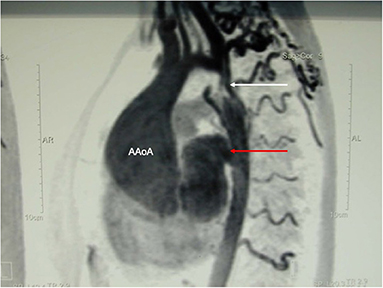

Two cases of huge aneurysm of the proximal descending aorta following different coarctation repair

A 23-year old female was referred because of hemoptysis. She had had aortic coarctation repair with a prosthetic patch at the age of 6. Eight years later an ascending-descending bypass was performed because of re-coarctation. At admission, she presented with an ascending aortic aneurysm and a large pseudoaneurysm at the distal anastomosis of the previous extra-anatomic bypass that was itself partially thrombosed. The proximal descending aorta was highly narrowed (Figure 10). A small peripheral aorto-bronchial fistula was suspected as cause of the hemoptysis because it could not be identified during bronchoscopy. Operative repair was performed under double arterial canulation (aortic for the upper body and femoral artery for the lower body perfusion). The procedure was performed through mid-sternotomy and left hemi-clamshell and consisted in double ligation of the descending aorta proximally and distally of the end-to-side previous bypass anastomosis in order to exclude the pseudo-aneurysm. The ascending aortic aneurysm was resected and the aorta replaced with a prosthetic vascular graft and finally, an ascending-descending bypass was performed to restore continuity between the ascending with the distal descending aorta (Figure 11). The suspected site of the aorto-bronchial fistula was addressed by a small wedge-resection and the suture line covered with a intercostal muscle flap. Postoperative recovery was uneventful.

FIGURE 10

www.frontiersin.org

Figure 10. MR-angiography showing a large aneurysm of the ascending aorta (AaoA), a hypoplastic aortic arch and a recurrent stenosis following previous coarctation repair (white arrow) and enlarged intercostal arteries as sign of collateralization. In addition, there was a large pseudoaneurysm at the site of a Dacron patch used for initial coarctation repair (red arrow).